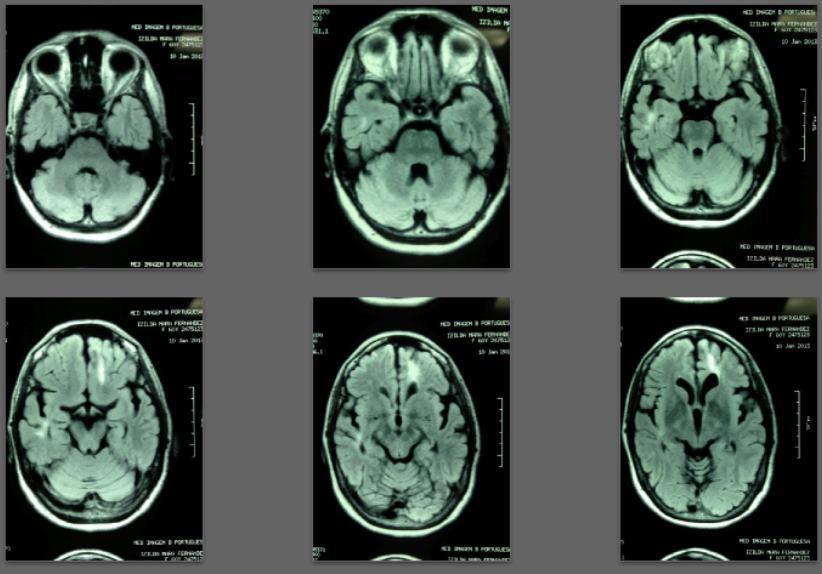

Before/after MRI images for one of 1,000+ patients of Dr. Coimbra

2008 Convulsive seizures Diagnosis: Balo’s concentric hemiparesis

Starting daily dose 25,000 IU; increased in stages to 80,000 IU on October 28, 2010. Asymptomatic since 2010.

2008 MRI